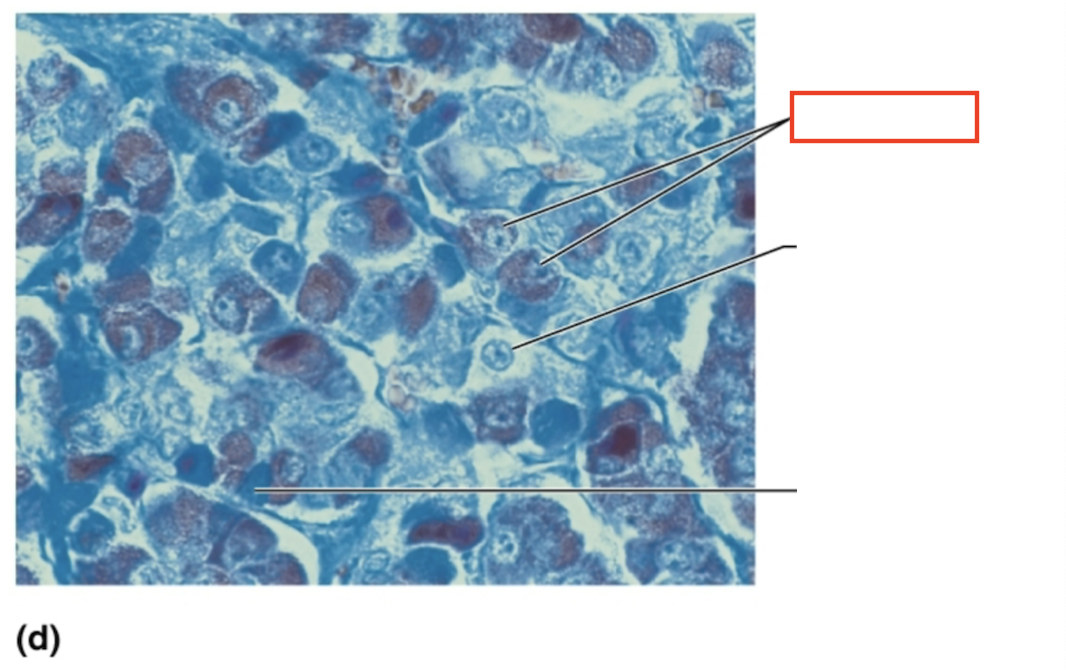

What structure is highlighted?

acidophils

What structure is highlighted?

chromophobe

What structure is highlighted?

basophil

What tissue is shown?

anterior pituitary